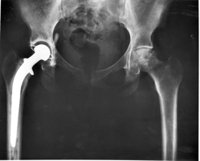

La realización de un programa de ejercicios en casa para los pacientes que completaron la rehabilitación estándar tras una fractura de cadera mejora la función física, según los resultados de un estudio que se publican este miércoles en la revista 'JAMA'. El tratamiento en el hogar consiste en realizar ejercicios como ponerse de pie desde la posición de sentado en una silla o subir un escalón.

Más de 250.000 personas en Estados Unidos se fracturan la cadera cada año y muchos de experimentan consecuencias graves a largo plazo. "Dos años después de una fractura de cadera, más de la mitad de los hombres y el 39 por ciento de las mujeres han fallecido o viven en un centro de cuidados a largo plazo. Muchos de ellos ya no son capaces de realizar tareas funcionales básicas completas independientemente de que pudieran llevarlas a cabo antes de la la fractura, como dar la vuelta a la manzana o subir cinco escalones dos años después de una fractura", según la información de respaldo del artículo.

La directora de este estudio, Nancy K. Latham, de la Universidad de Boston, en Estados Unidos, y sus colegas asignaron al azar a 232 adultos mayores funcionalmente limitados que habían completado la rehabilitación tradicional después de una fractura de cadera a un programa de ejercicios de cadera en casa que comprende algunos de orientación funcional (como ponerse de pie desde una silla o subir un escalón) impartido por un fisioterapeuta y realizado de forma independiente por los participantes en sus casas durante seis meses (120 participantes) o educación sobre nutrición cardiovascular en casa y por teléfono (112).